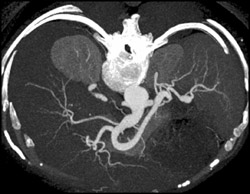

Median Arcuate Ligament Syndrome